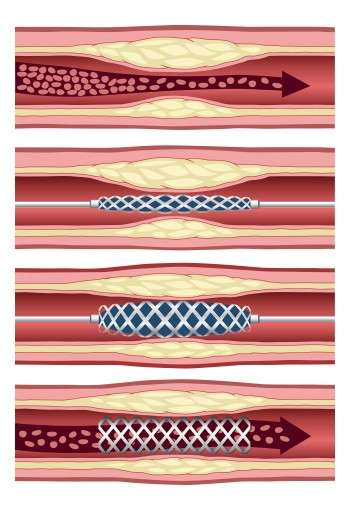

Stenting of the so-called “culprit vessel” is known as primary percutaneous coronary intervention (PCI). Researchers from the Ottawa Heart Institute, led by cardiology resident Juan Russo, MD, used patient records in the Institute’s STEMI registry to understand whether it is safe to stent the non-culprit vessels at a time following primary PCI but before patients leave the hospital. This approach is called staged PCI.

They examined the records of 1,038 STEMI patients referred to the Heart Institute between 2004 and 2011 who had a blockage of greater than 50% in at least one non-culprit vessel. One quarter of these patients had undergone staged PCI, while three quarters had PCI of the culprit vessel only.